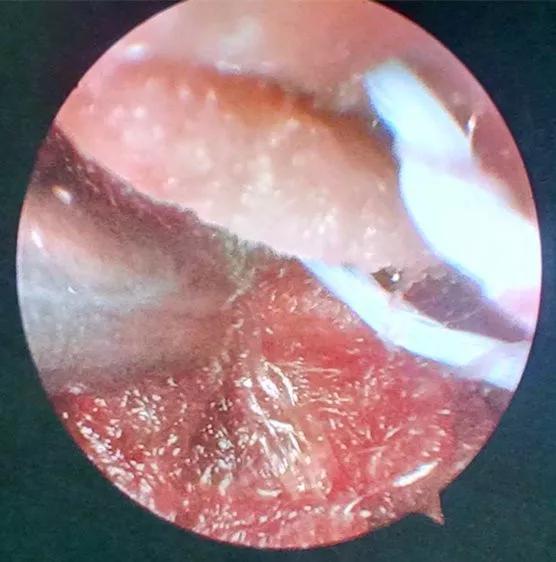

患者病情危重,出血点位于后颅窝靠近天幕,位置狭小、深在、靠近脑干、直视困难,应用普通手术操作困难,容易损伤脑干,血肿也不容易彻底清除。主管主任医师王占尧对该患者进行了详细的查体后,与治疗小组商议手术方案。为进一步减少小脑皮层损伤、降低颅脑创伤,王占尧主任医师决定对该患者使用内镜辅助清除血肿。

诊疗小组在王占尧主任医师的带领下,制定了详尽的手术方案。由王占尧主任医师主刀、贺中正医师辅助为患者实施了神经内镜下血肿清除术,患者术后恢复良好。